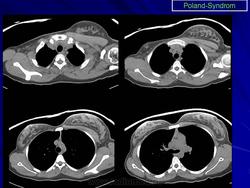

Синдром Поланда (СП) представляет собой комплекс пороков, включающий отсутствие большой и малой грудной мышц, синдактилию, брахидактилию, ателию (отсутствие соска молочной железы) и/или амастию (отсутствие самой молочной железы), деформацию или отсутствие нескольких ребер, отсутствие волос в подмышечной впадине и снижение толщины подкожно-жирового слоя. Отдельные компоненты этого синдрома впервые были описаны Lallemand LM (1826) и Frorier R (1839). Однако назван он по имени английского студента-медика Alfred Poland, который в 1841 году опубликовал частичное описание данной деформации. Полную характеристику синдрома в литературе впервые опубликовал Thompson J в 1895 году.

Поланда синдром (Poland syndrome)